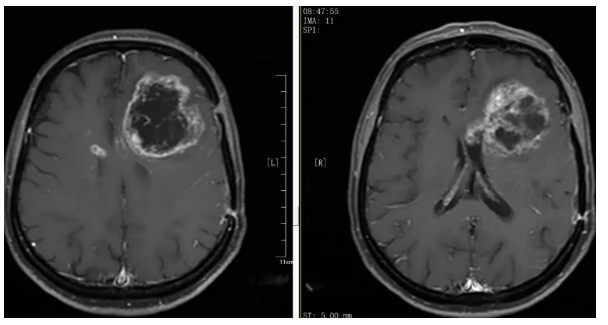

入院后,银丰(济南)医院神经肿瘤科团队第一时间完善颅脑MRI及血常规、肝肾功能、电解质等检查,全面评估患者病情与身体状况。结果显示:左侧额叶病变较大,占位效应明显,若不及时干预,将进一步压迫脑组织,引发更严重的神经功能障碍,甚至危及生命。

左额叶巨大占位并侵犯胼胝体,中线移位明显,对侧出现小转移灶